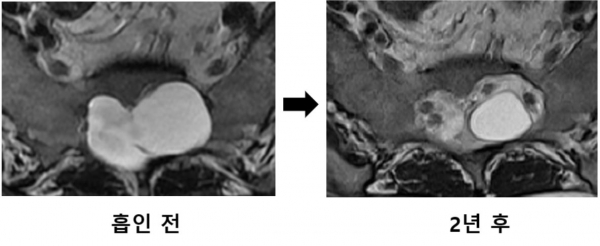

논문에 따르면 탈로브씨 낭종 증후군 환자에게 이 시술을 시행해 척추 물혹 안의 뇌척수액을 뽑아낸 결과, 통증이 유의미하게 호전됐고 2년 후 촬영한 MRI에서도 척추 물혹이 시술로 작아진 크기를 유지하며 척추 신경을 압박하지 않는 것으로 확인됐다.

보통 흡인 주사치료 후 재발이 흔한데 비해 줄어든 낭종 크기가 2년 이상 유지된 것이다.